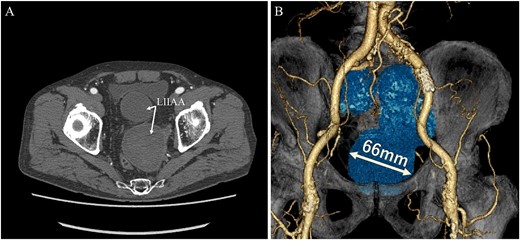

A 68-year-old male was admitted for the expansion of a left IIAA. He had undergone coiling of peripheral branches and stent graft placement in the left common iliac artery (CIA) 10 years prior. Eight years prior, an endoleak was detected between the left CIA and the left IIA. This led to the patient undergoing Y-grafting and disconnection of the CIA and IIAA. Contrast-enhanced computed tomography (CT) revealed a giant IIAA, with a maximum short diameter of 66 mm, and no signs of endoleak (Fig. 1). The aneurysm presented as a cluster of three separate lobes, resembling a dumpling-like structure.

Preoperative computed tomography imaging showing a giant left internal iliac artery aneurysm in a dumpling-like cluster with a maximum short diameter of 66 mm. A—Axial image, B—3D image. LIIAA, left internal iliac artery aneurysm.